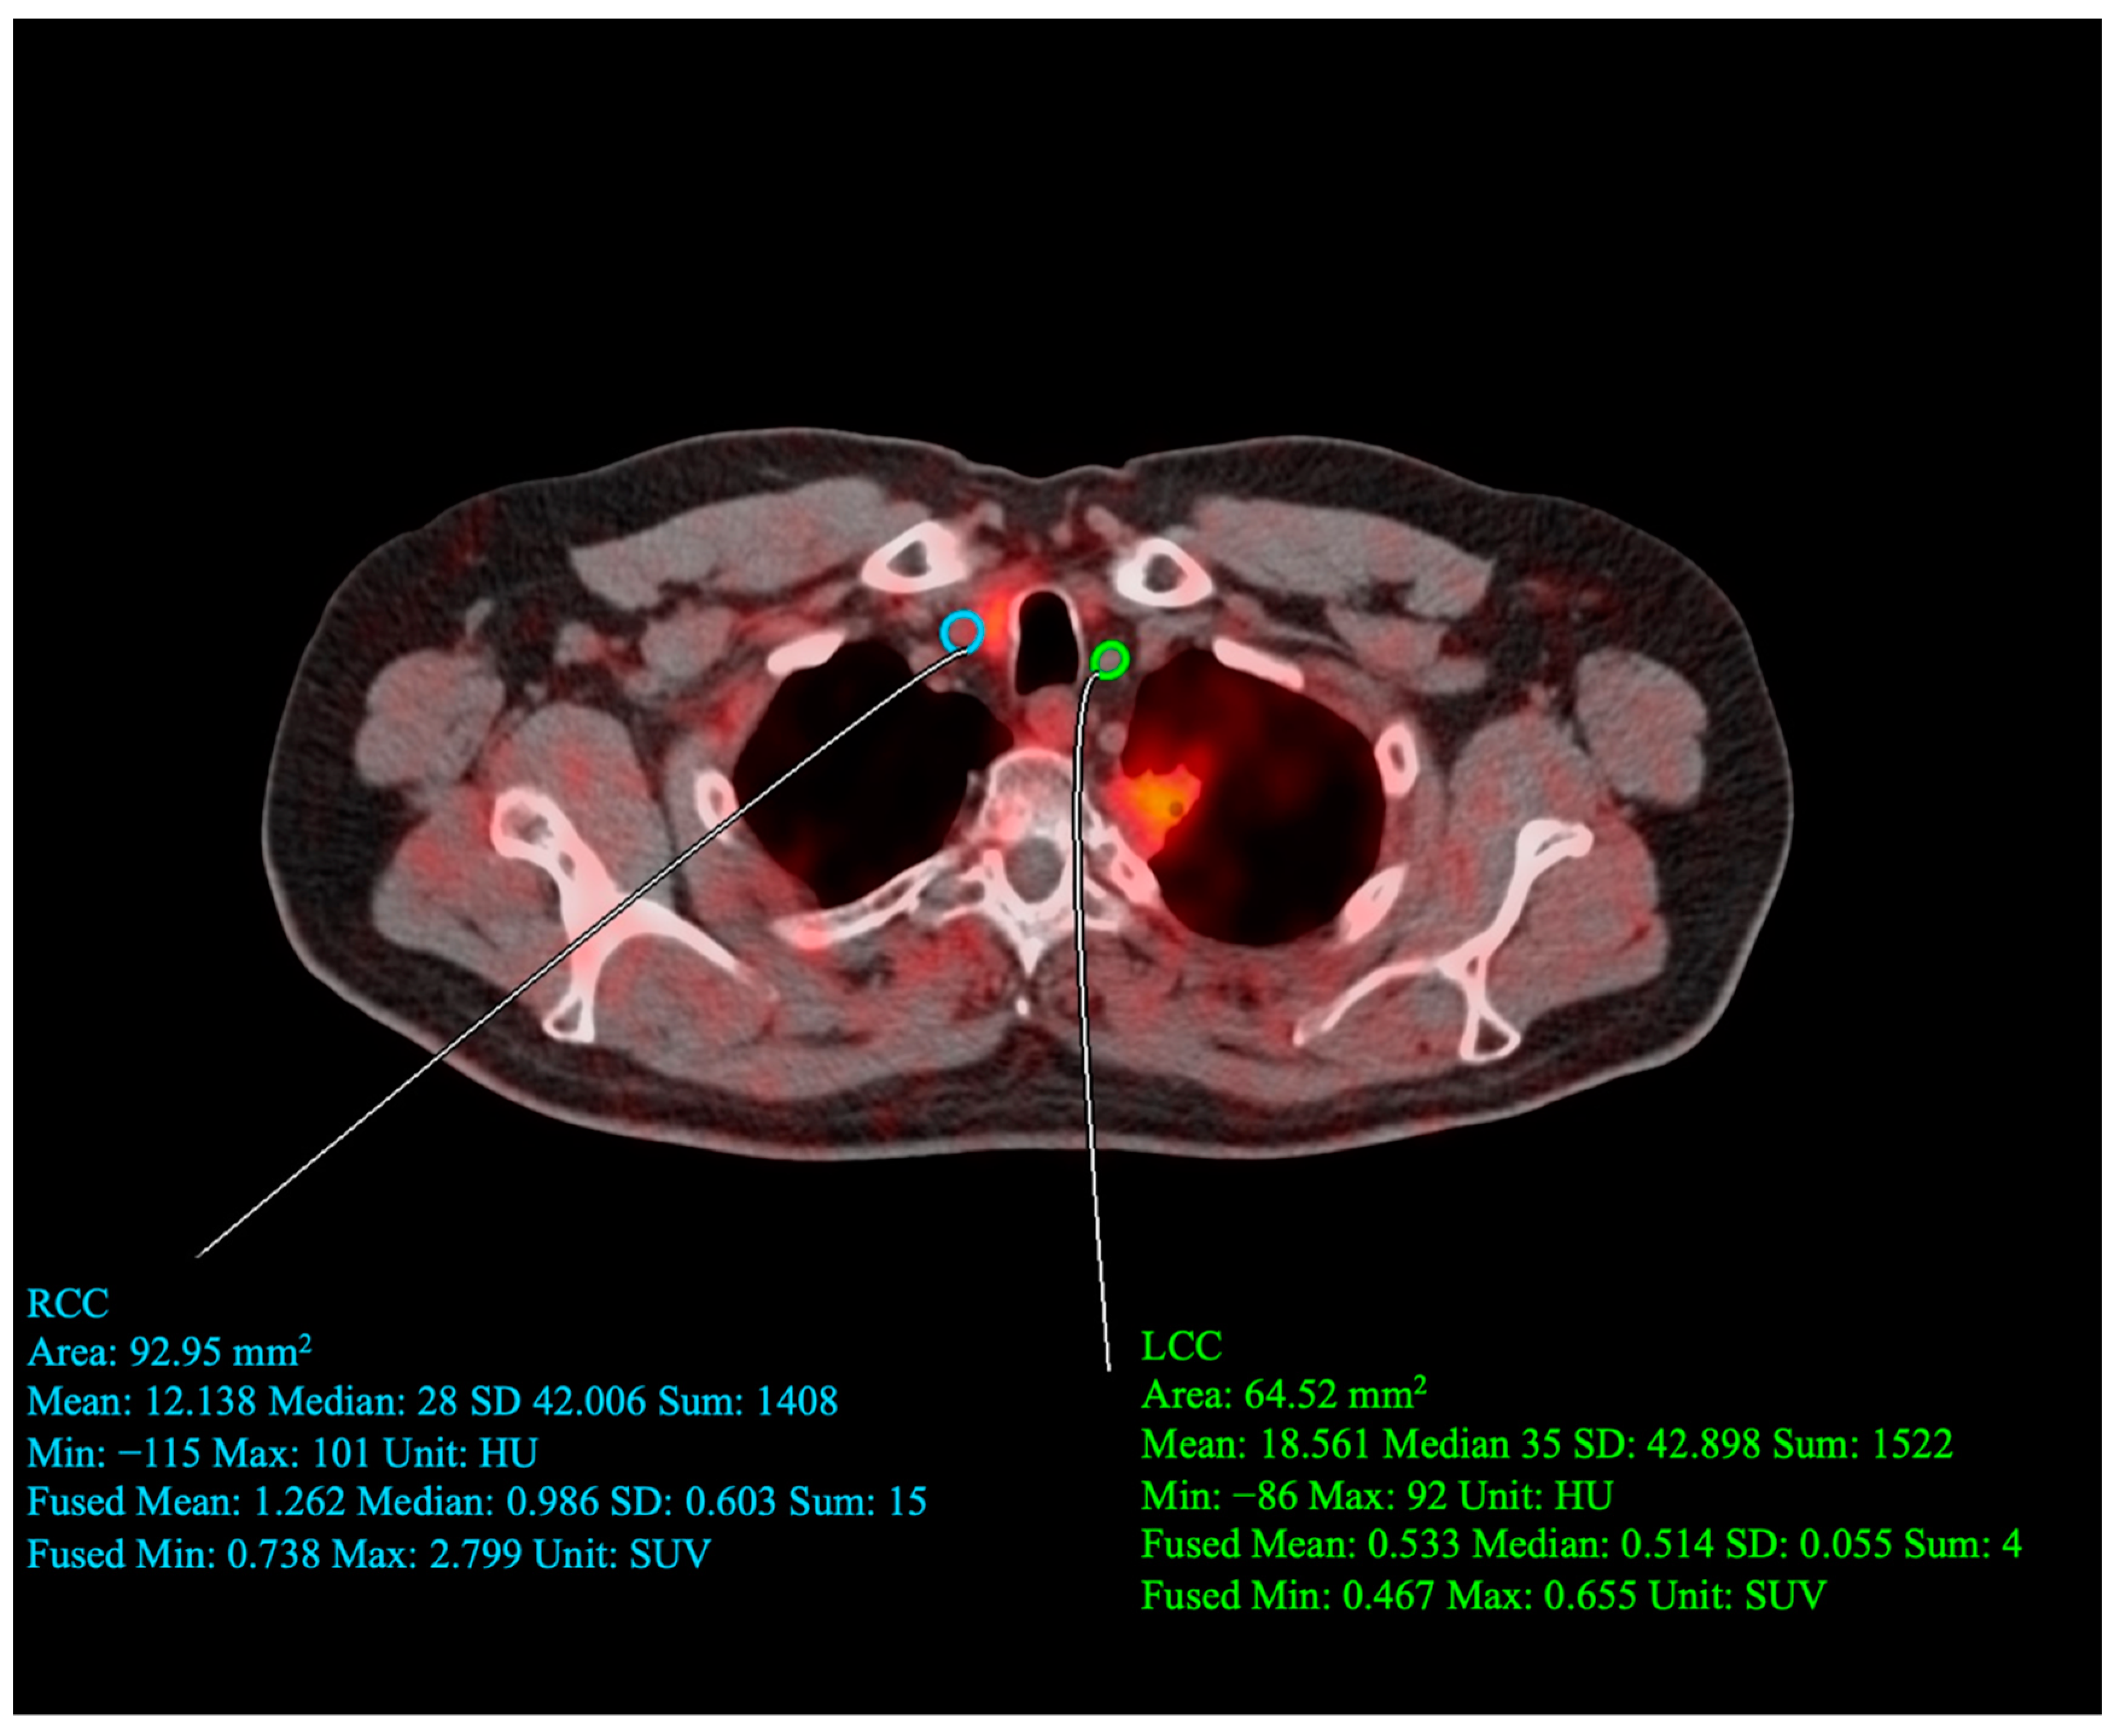

2.5. Carotid PET/CT Acquisition Protocol

2.6. Carotid PET/CT Data Analysis